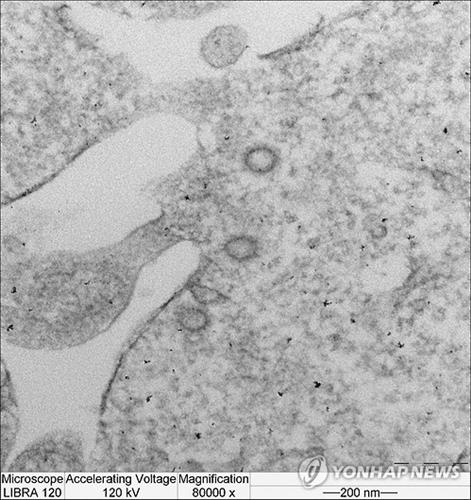

게르트 주터 교수가 이끄는 연구팀은 마부르크 대학과, 에라스무스 메디컬센터와 공동으로 메르스 후보 백신 'MVA-MERS-S'를 개발, 쥐를 대상으로 예비 임상시험을 진행해 그 결과를 5월 바이러스학 저널에 실었다.

메르스 바이러스에 대한 백신은 아직 개발되지 않았으며 세계보건기구는 후보 백신들이 사전임상단계까지 개발된 상태라고 밝힌 바 있다.